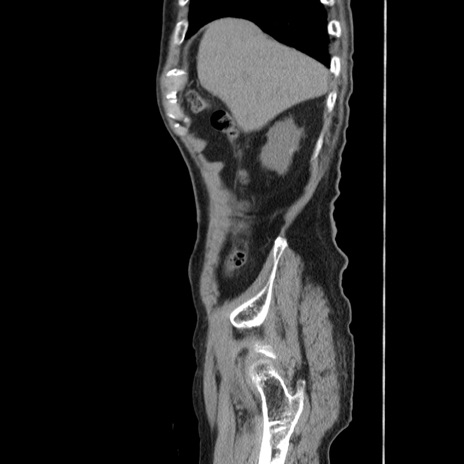

症例24(矢状断像)

冠状断像